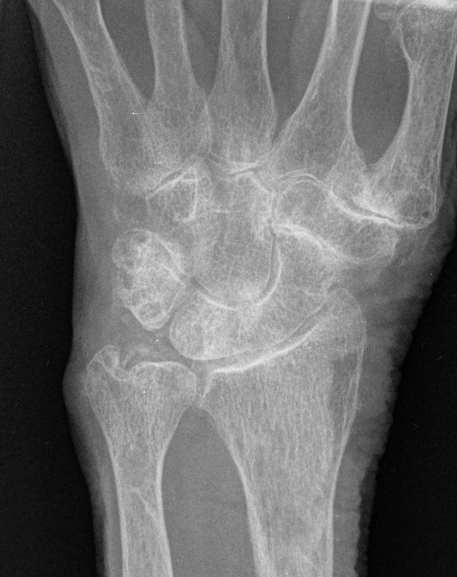

3. Scapholunate coalition